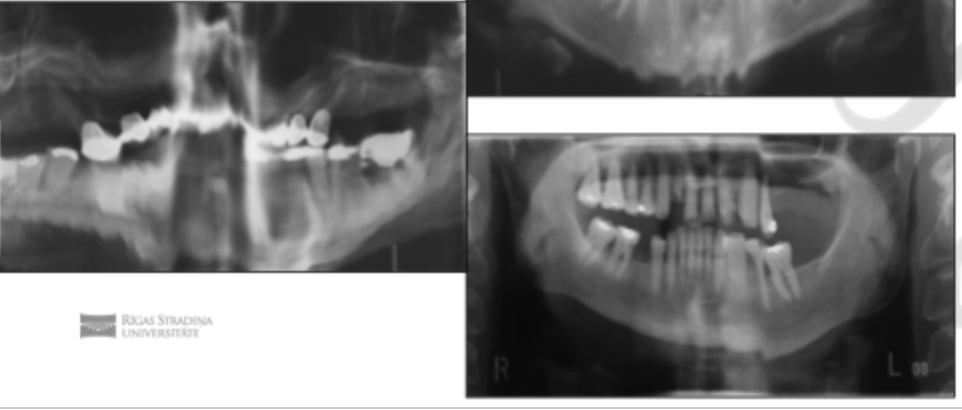

Review/Montior

TMJ joint changes → overview of condyles & joint area

Cons of OPG & CBCT

OPG

Lower resolution than intraorals, geometric distortion, positioning sensistive, not ideal for caries diagnosis.

CBCT

Higher radiodose than 2D imaging, more ecpensive, metal artifacts, Not for soft tissue imaging, overuse w/o indication (ALARA), training to interpret, Motion artifacts.